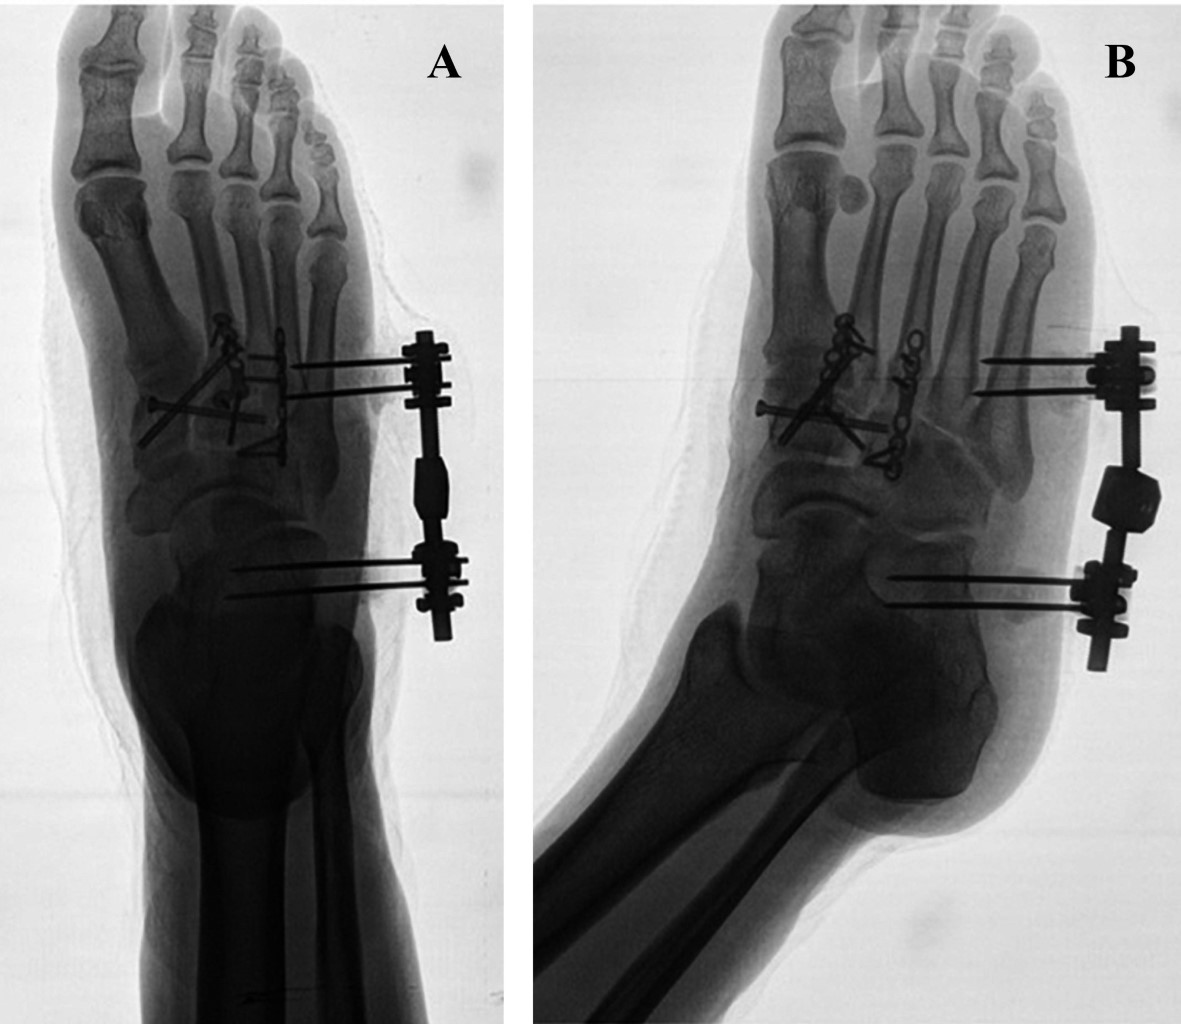

Figure 2